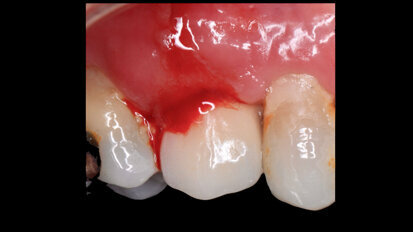

Los “milagros” de la Ortodoncia Exprés

El autor comenta que los tratamientos “milagrosos” de ortodoncia y diseño de sonrisa que con frecuencia se ven en internet suelen tener consecuencias ...